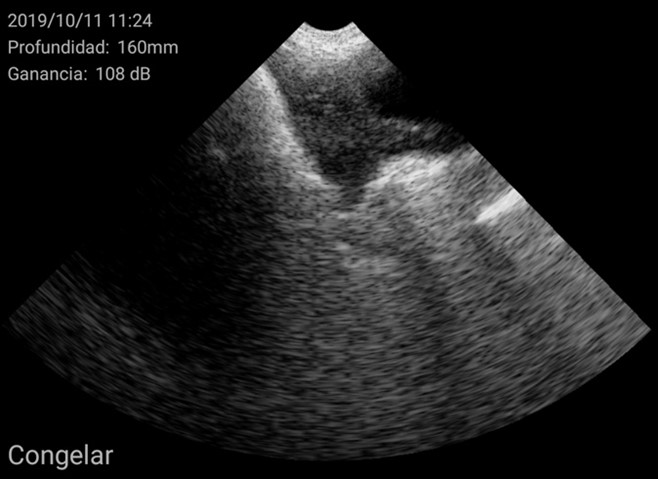

Por el contrario, úteros grandes, con cuernos uterinos identificables y que ocupan gran superficie de la pantalla se consideran como hembra púber.

Imágenes de cerdas Púberes con el ecógrafo W3 de Kubus

Además, se pudieron identificar otras estructuras como éste ovario con cuerpos hemorrágicos y un folículo central no ovulado, característico de una cerda en metaestro: